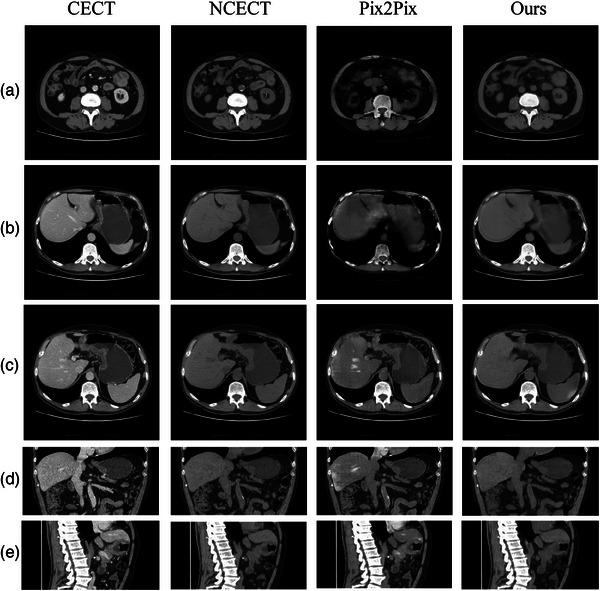

A deep network was developed to convert CECT to NCECT. The network receives a 3D image from CECT images as input and generates a corresponding contrast-removed NCECT image patch. Abdominal CECT and NCECT image pairs of 20 patients were deformably registered and 8000 image patch pairs extracted from the registered image pairs were utilized to train and test the model. CTs of clinical proton patients and their treatment plans were employed to evaluate the dosimetric impact of using the generated NCECT for proton dose calculation.

Our approach achieved a Cosine Similarity score of 0.988 and an MSE value of 0.002. A quantitative comparison of clinical proton dose plans computed on the CECT and the generated NCECT for five proton patients revealed significant dose differences at the distal of beam paths. V100% of PTV and GTV changed by 3.5% and 5.5%, respectively. The mean HU difference for all five patients between the generated and the scanned NCECTs was ∼4.72, whereas the difference between CECT and the scanned NCECT was ∼64.52, indicating a ∼93% reduction in mean HU difference.